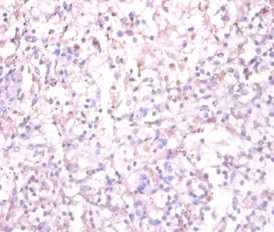

Immunohistochemistry of paraffin-embedded human spleen tissue using CSB-PA09674A0Rb at dilution of 1:100